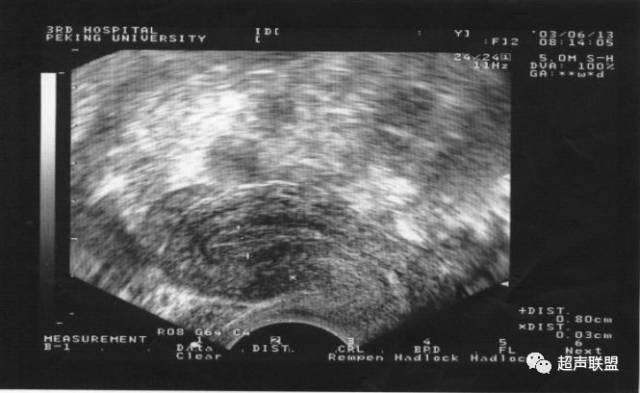

目前最常用的方法是配合基礎體溫測定的陰道超聲波監測,它通過跟蹤監測優勢卵泡,最能客觀反映卵泡生長發育狀況,觀察是否有排卵,並同步反映子宮內膜的發育狀況。

卵泡監測的一般方案

對於月經周期28~30天的女性,優勢卵泡從月經周期的第6~8天開始發育,您初次監測的時間可以在月經周期的第11~12天,之後根據優勢卵泡的大小來決定下一次的監測時間,中心制定了一套監測程序:

最大的卵泡直徑<10mm時,下次監測的時間間隔為6~7天;

優勢卵泡直徑10~12mm時,下次監測的時間間隔為3~4天;

優勢卵泡直徑13~15mm時,下次監測時間間隔為2~3天;

當優勢卵泡直徑16mm以上時,下次監測時間間隔為1~2天;

自然周期待體溫上升後,超聲波監測卵泡是否消失或塌陷,預示已經排卵。促排卵周期或人工授精周期,在卵泡直徑>18~20mm時,預示卵泡已經成熟,可以注射HCG,48小時後觀察卵泡是否已經排掉。

通常每個周期超聲波監測的次數應控制在3~4次,這是一種比較經濟和準確的超聲波監測方案。

卵泡三維成像

當優勢排卵發育成熟至直徑18~23mm,自然周期可以自測基礎體溫,升高>0.2℃(大約36.7°以上)後複查超聲波,觀察是否已經發生排卵。

發育中的卵泡

優勢卵泡